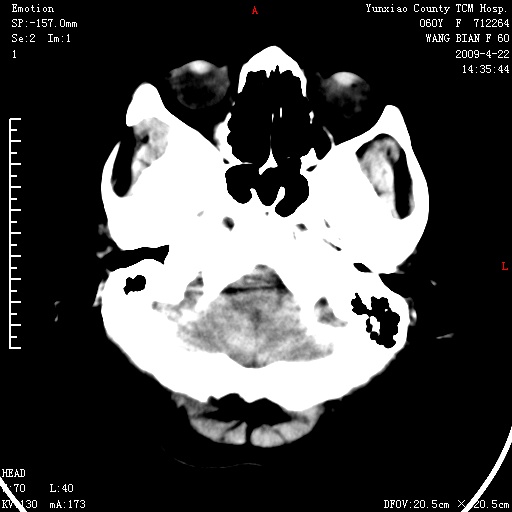

标题: CT19525:体检

蛛网膜颗粒压迹 左肾低密度影囊肿可能。

1、头颅未见明显异常。

2、左肾囊肿。

1、头颅未见明显异常。2、左肾囊肿可能。建议增强

1、枕骨蛛网膜粒压迹。2、左肾囊肿可能。建议增强

1)枕骨蛛网膜粒压迹。2)左肾囊肿可能。